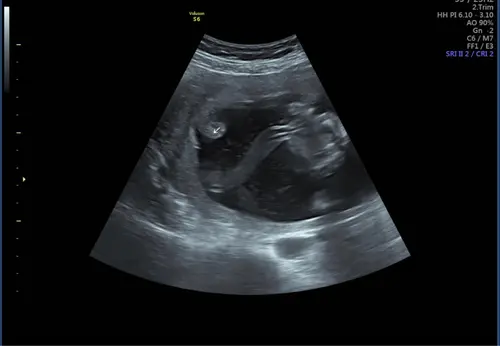

Hey! Ik heb dat ook gehad, zelfs ik kon het extreem duidelijk zien op de echo met 20 weken toen ze het me vertelde. Enorme krullen naar binnen. Toen naar uni doorgestuurd en is bevestigd. Allerlei extra groeicontroles gekregen. Uiteindelijk groeide m’n baby zelfs te hard (dat stond los van de geconstateerde afwijking) en ben ik zelfs met 38+4 ingeleid. Maar goed ook, het ventje was toen al 4.6 kg 😅 En toen m’n placenta geboren was vroeg ik of ze iets konden zien (aanwezige verloskundige wist van niets) en ze zagen 0.0, zelfs toen ik het daarna vertelde zeiden ze: oh is echt niet (meer?) zichtbaar.

Ik ben vandaag gaan terug kijken naar eerdere echo’s en daar zie je het eigenlijk ook al terug zelfs met krullingen etc zoals jij het noemt. Alleen is het toen nooit benoemd geweest dus ik heb de indruk dat ze er niet teveel van maken. Ik veronderstel dat ze het volgende week wel uitgebreid ter sprake gaan brengen aangezien de placenta ook nog steeds laag ligt. Ik krijg sowieso al veel meer controles dus dat is geruststellend… bedankt voor je berichtje! ♥️